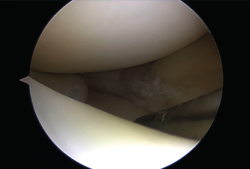

Biomecánicamente, se ha demostrado que una configuración de sutura vertical ya sea dentro-fuera o técnicas todo dentro cada 3 a 5 mm proporciona superioridad sobre la configuración horizontal(10)(Figura 4).

Figura 4. Asa de cubo: sutura con 3 puntos mediante técnica todo dentro.